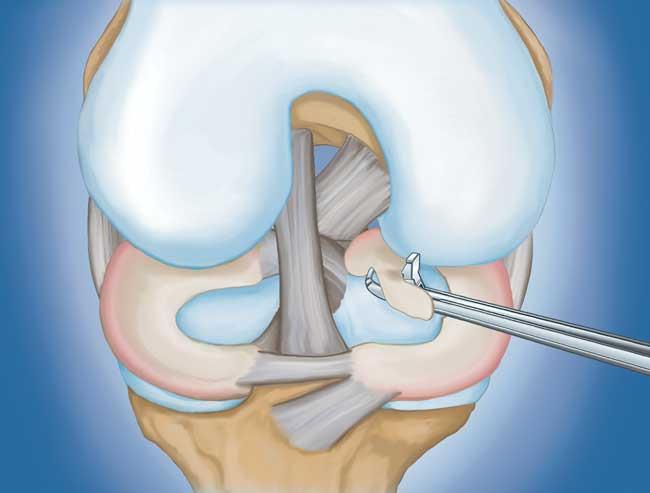

程序。 膝關節鏡檢查是最常進行的外科手術之一。在這個過程中,外科醫生通過膝蓋上的一個小切口(入口)插入一個微型相機。這提供了膝蓋內部的清晰視圖。然后外科醫生通過兩個或三個其他小入口插入手術器械以修剪或修復撕裂。

- 部分半月板切除術。 在這個過程中,受損的半月板組織被修剪掉。該程序通常允許在手術后立即負重和全方位運動。

在這段簡短的手術視頻中,半月板部分切除術期間使用電動剃須刀平滑了退行性半月板撕裂。

- 半月板修復。 一些半月板撕裂可以通過將撕裂的碎片縫合(縫合)在一起來修復。撕裂能否成功修復取決于撕裂的類型,以及受傷半月板的整體狀況。因為半月板必須一起愈合,修復的恢復時間比半月板切除術長。